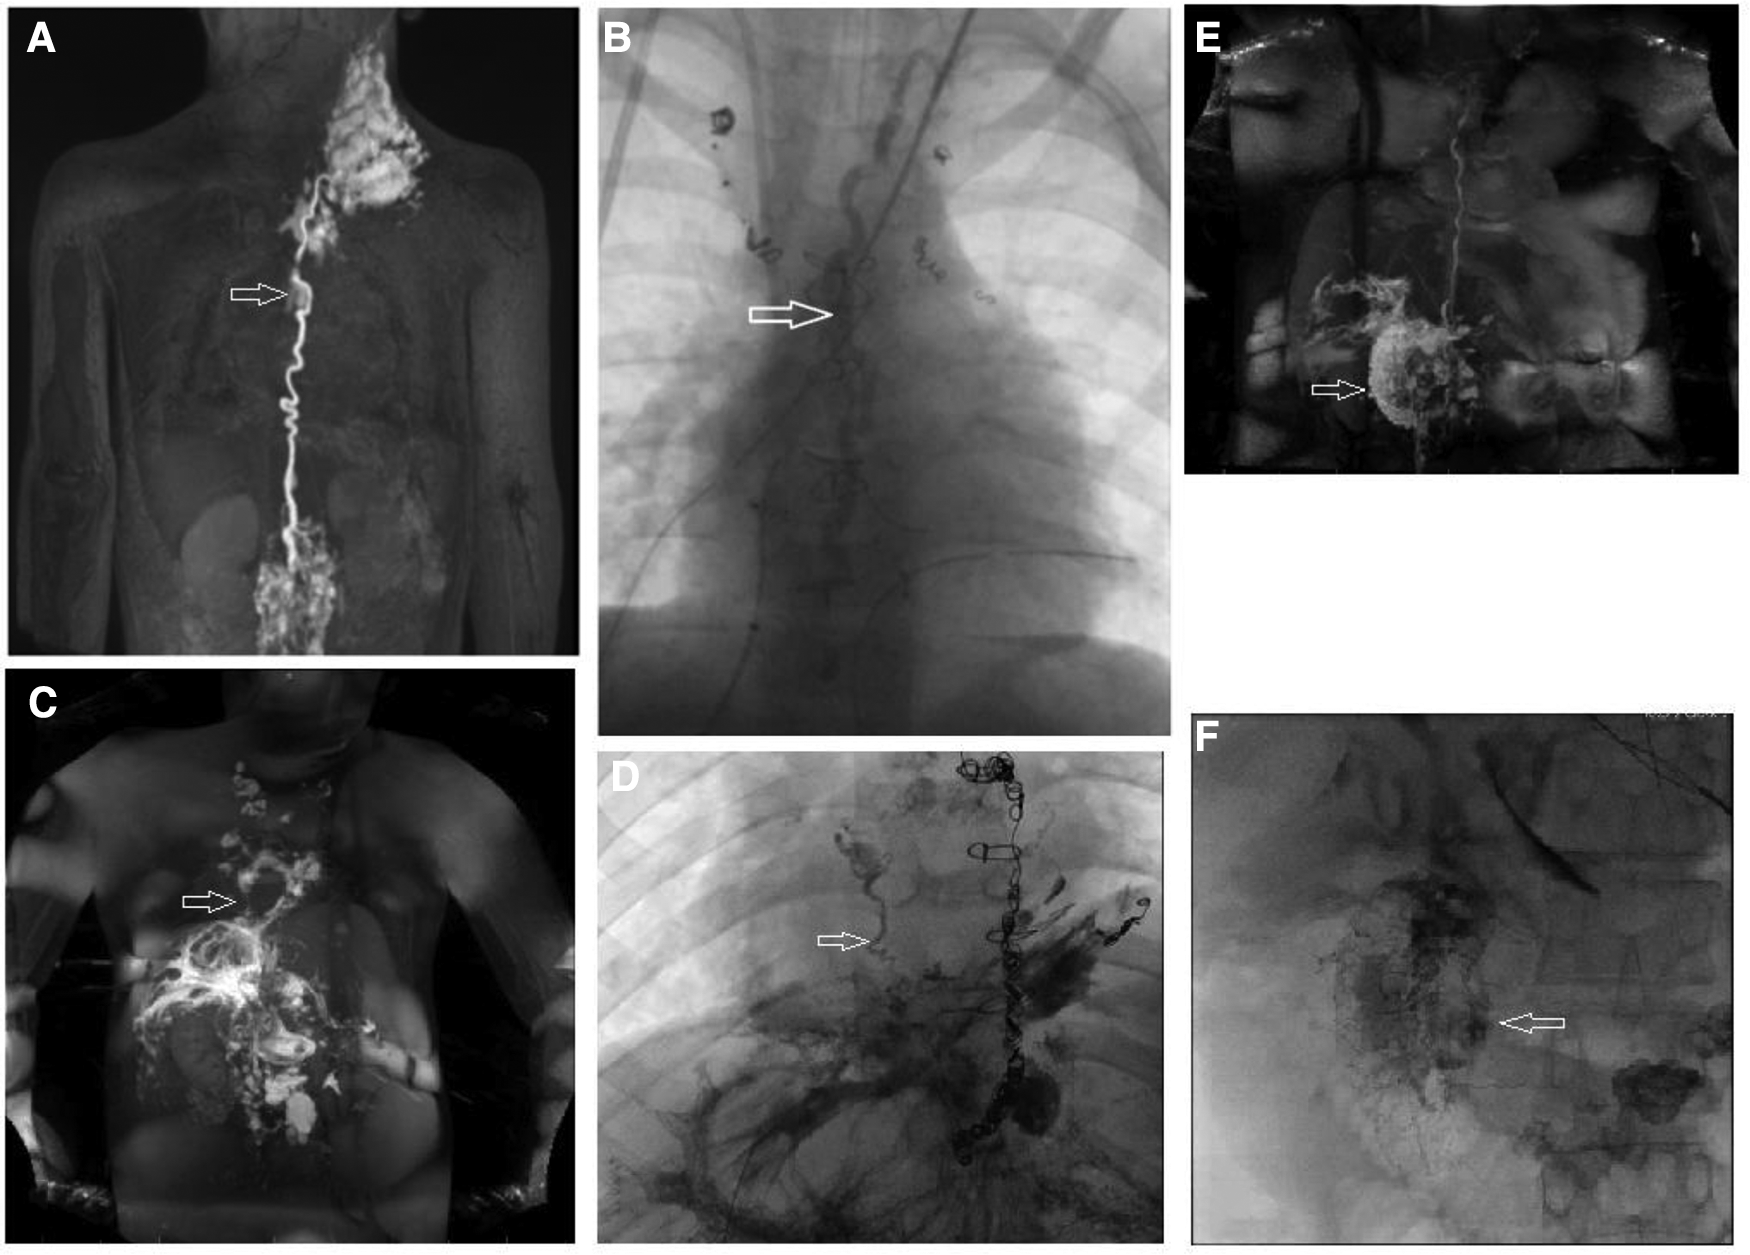

Conservative therapy alone is often insufficient in treating lymphatic disease in Fontan patients. Based on the current pathophysiologic understanding of lymphatic flow disorders a series of new minimally invasive and surgical techniques have been invented during the last decade with promising results. Lymphatic catheter-based interventions can now be provided to treat most lymphatic disease in specialized centers. They can be divided into two categories, those that are aimed to occlude abnormal lymphatic ducts and those that are meant to decompress the entire lymphatic system (25). Several techniques have been proposed to selectively occlude abnormal lymphatic channels using glue, coils, or a combination (46, 79). Thoracic duct embolization was first described (80). It involves the transabdominal cannulation of the thoracic duct with a 22–24 gauge spinal needle, the introduction of a microcatheter and administering of a lipiodol glue emulsion that occludes the central lymphatic system (Figures 11A, B). Alternatively the thoracic duct can be accessed retrogradely (81). Thoracic duct embolization was successfully performed in patients with postoperative chylothorax and plastic bronchitis but if possible it should be avoided in Fontan patients because it can lead to the development of downstream lymphatic complications like protein loosing enteropathy or ascites (52, 80, 82). Nowadays a more selective approach is preferred whenever possible (Figures 11C, D) (33, 52, 83, 84). During selective lymphatic duct embolization procedures the microcatheter in the thoracic duct is further advanced into side branches or directly into small lymphatic fistulas that can subsequently be embolized. Sometimes a second microcatheter is placed in the thoracic duct and flushed with glucose during glue administration to prevent carryover of glue into the thoracic duct. In protein losing enteropathy patients abnormal lymphatic networks can selectively be punctured in the liver or the intestinal wall with a 25-gauge spinal needle with a similar approach used in liver lymphatic imaging (Figures 11E, F) (85). After endoscopic confirmation of an abnormal connection to the duodenum with blue dye these channels can then be sealed with glue. Another minimally invasive procedure that occludes lymphatic flow is ethiodized oil embolization. Lipiodol is an iodinated contrast agent that leads to sclerosis in small lymph vessels. It can be administered through a microcatheter or via needles placed in the inguinal lymph nodes. The latter strategy had been demonstrated to be successful in the treatment of chylothorax (86–88).

Figure 11

Different types of lymphatic interventions. (B) AP fluoroscopic imaging after thoracic duct embolization (arrow) in a 5 year old patient. (A) Corresponding preinterventional IN-DCMRL. (C) MIP coronal projection of IH-DCMRL in a 12 year old patient with plastic bronchitis demonstrating hepatopulmonary connections (arrow). (D) AP fluoroscopic image showing the hepatopulmonary connection after selective embolization (arrow). (E) Coronal projection of intrahepatic dynamic contrast magnetic resonance lymphangiography in a 21 year old patient with PLE demonstrating leak into the duodenum. (F) Fluoroscopic imaging of the duodenum after periduodenal (arrow) lymphatic embolization in the same patient.